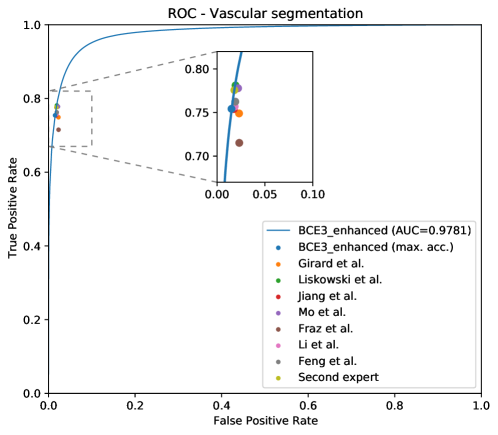

As commented in the previous sections, we include three ROC and PR curves, one for each structure of interest: arteries (A), veins (V), and Vascular Tree (VT)—that is, vessels—. Figure 9 depicts the ROC and PR curves for the different networks in the DRIVE-test set.

Finally, in order to provide a context for the performance in the vasculature segmentation of the proposed system, we provide a comparison with reference works aiming at the vasculature segmentation in Table 5. Also, we complement the results shown in this table with the ROC curve depicted in Figure 16, as it was done for the RITE-test results. The reported results use the DRIVE-test set, which is composed of the same images as in the RITE-test set. However, in this case, the ground truth segmentations considered as gold standard are those provided by the first expert, and thus the obtained results are slightly different from the results reported for RITE.

As it can be observed in the comparison results, the proposed approach achieves highly competitive results in both the artery/vein classification and the vascular segmentation tasks. In this regard, it is especially relevant that our approach achieves the best performance in the vascular segmentation task among the works aiming at solving both SSCAV tasks, and even a competitive performance with the state-of-the-art specialized methods. This is particularly relevant since, in a real A/V classification scenario, only the detected vessels would be classified into arteries and veins. Regarding the artery/vein classification of the ground truth vessels, however, the achieved results are slightly below the most recent works [40, 41].